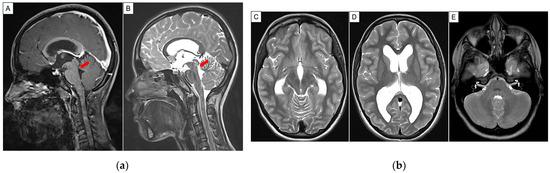

Hyponatremia Following Endoscopic Third Ventriculostomy in an Adolescent with an Aqueductal Web: A Case Report

by Tingting Feng, Lee Ping Ng, Wan Tew Seow and Sharon Y. Y. Low

Reports 2026, 9(2), 122; https://doi.org/10.3390/reports9020122 - 17 Apr 2026

Background and Clinical Significance: Endoscopic third ventriculostomy (ETV) is a well-established cerebrospinal fluid (CSF) diversion technique for treating obstructive hydrocephalus. Here, the complication of post-ETV hyponatremia is rare. Separately, aqueductal web as a cause of obstructive hydrocephalus is also an uncommon occurrence. We [...] Read more.

Background and Clinical Significance: Endoscopic third ventriculostomy (ETV) is a well-established cerebrospinal fluid (CSF) diversion technique for treating obstructive hydrocephalus. Here, the complication of post-ETV hyponatremia is rare. Separately, aqueductal web as a cause of obstructive hydrocephalus is also an uncommon occurrence. We present an unusual case of an adolescent who presented with late symptoms of obstructive hydrocephalus secondary to an aqueductal web and developed a delayed onset of post-operative hyponatremia after a successful ETV procedure. Pertinent aspects of the case are discussed in corroboration with the recent literature. Case Presentation: A previously well 14 year old presented with symptoms of raised intracranial pressure. Neuroimaging demonstrated progressively enlarging ventricles associated with an aqueductal web. She underwent an uneventful ETV and was discharged home. However, she was readmitted for symptomatic hyponatremia that was investigated and most likely attributed to Syndrome of Inappropriate Antidiuretic Hormone Secretion (SIADH). She was managed with fluid restriction with good clinical improvement. Conclusions: We herein report a case of delayed onset of obstructive hydrocephalus secondary to an aqueductal web, treatment challenges faced and the patient’s unexpected occurrence of hyponatremia after a technically successful ETV. This emphasizes that clinicians need to be mindful of this potential post-operative complication and the ability to discern subtle symptoms in a patient whose clinical signs may not be straightforward. Full article